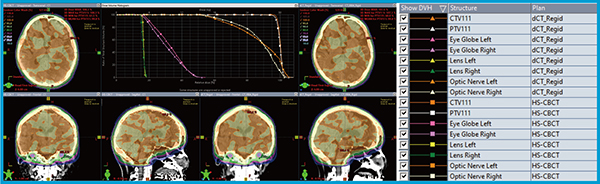

● 症例2:第4腰椎から左骨盤骨の骨転移に対する緩和照射 25Gy/5Fr(PTV D50処方)

腸管ガスによるアーチファクトを懸念し,IDENTIFYを併用した自然呼気息止め(10秒程度)にて撮影した。dCT画像は,放射線治療計画支援システム「Velocity」(バリアン社製)を用いて非剛体レジストレーションを行った。PTVの最大線量の差は1.3%,総MUの誤差は0.3%(3.1MU)であり,DVHは全体としておおむね一致した(図5)。一方,膀胱および消化管のDVHに認められたわずかな差異は,腸管ガスの位置・量の違いに起因すると推察された。

図5 症例2におけるHS-CBCT(左)とdCT(右)の線量分布の比較